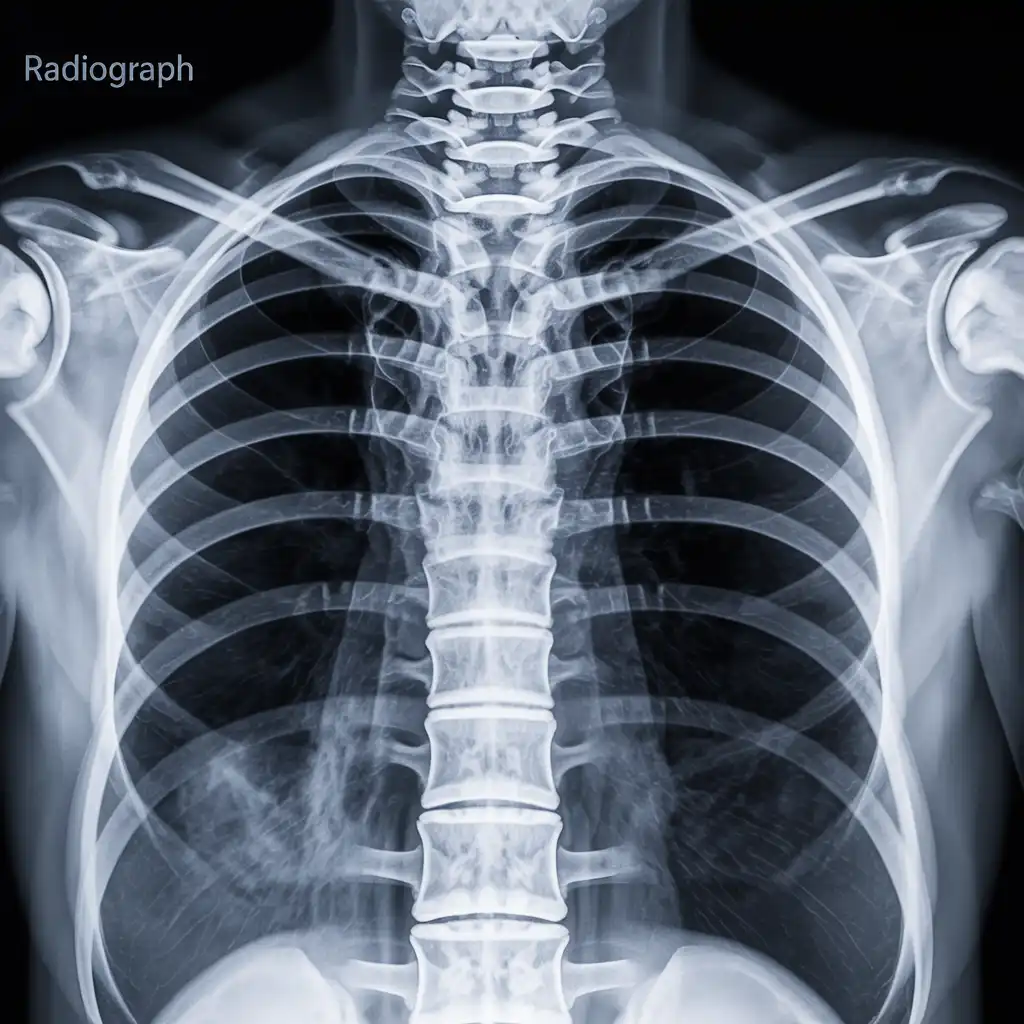

Siamo un gruppo di tecnici di radiologia abilitati, con una lunga esperienza maturata in reparti ospedalieri e strutture diagnostiche del territorio. Abbiamo scelto di portare la nostra competenza direttamente nelle case dei pazienti, offrendo esami radiologici a domicilio con standard elevati di qualità e sicurezza.

Nel corso degli anni abbiamo effettuato migliaia di radiografie a domicilio in abitazioni private, RSA, centri di assistenza e strutture per anziani, utilizzando apparecchi digitali portatili certificati che garantiscono immagini precise e tempi di esecuzione rapidi.

Con Radidom Salerno poniamo la persona al centro: attenzione, professionalità e tecnologia avanzata per offrire un percorso diagnostico comodo, umano e totalmente accessibile anche a chi ha difficoltà negli spostamenti.